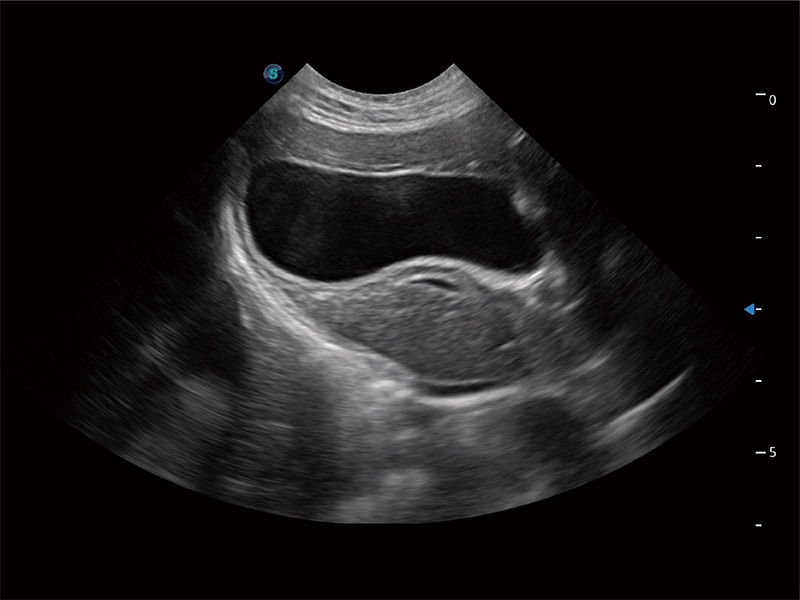

(猫)胆囊

(犬)胎儿四腔心